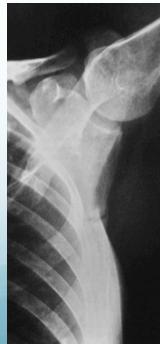

Characteristic Sign: Looser’s Zones

- Poorly healing stress fractures typically occurring at:

- Neck of scapula

- Looser’s Zones (pseudo fractures). z

Looser’s zones Z are short lucent bands running through the cortex at right angles, usually going only part way across the bone